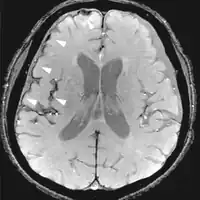

| Effective T2 or "T2-star" | T2* | Spoiled gradient recalled echo (GRE) with a long echo time and small flip angle[11] | Low signal from hemosiderin deposits (pictured) and hemorrhages.[11] |  | |

| Susceptibility-weighted | SWI | Spoiled gradient recalled echo (GRE), fully flow compensated, long echo time, combines phase image with magnitude image[12] | Detecting small amounts of hemorrhage (diffuse axonal injury pictured) or calcium.[12] | _in_diffuse_axonal_injury.jpg.webp) | |